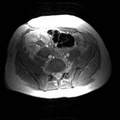

RADIOLOGY: KIDNEY: Case# 33985: PTLD. Renal transplant patient. 1) Echogenic mass with cystic component in the renal transplant hila causing focal stenosis in the main renal artery. The appearance would be most consistent with post-transplant lymphoproliferative disorder. Alternatively, renal abscess in this area cannot be excluded. Correlation with clinical history recommended. 2) Marked hydronephrosis with internal debris within the collecting system of the transplant kidney. This is felt to likely be due to obstruction from the above mass. 3) Small bilateral pleural effusions and small amount of ascites.